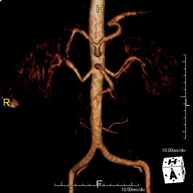

Prueba diagnóstica no invasiva que consiste en el estudio de la arteria aorta abdominal, obteniendo imágenes de alta definición anatómica mediante el empleo de un campo electromagnético y ondas de radio (con un emisor y un receptor). Es indispensable el uso de contraste paramagnético (Gadolinio). Sin embargo, no utiliza radiación ionizante. La calidad de las imágenes permite realizar reconstrucciones en 2D y 3D. Está indicado en aquellos pacientes con enfermedad vascular (aterosclerosis), estudio de aneurismas, en estudios pre-quirúrgicos de lesiones adyacentes a la aorta abdominal como "mapa" vascular, etc. - Angio RM Aorta-ilíaca

Prueba diagnóstica no invasiva que consiste en el estudio de la arteria aorta abdominal de las arterias ilíacas, obteniendo imágenes de alta definición anatómica mediante el empleo de un campo electromagnético y ondas de radio (con un emisor y un receptor). Es indispensable el uso de contraste paramagnético (Gadolinio). Sin embargo, no utiliza radiación ionizante. La calidad de las imágenes permite realizar reconstrucciones en 2D y 3D. Esta prueba está especialmente indicada como estudio pre-quirúrgico (mapa vascular) antes de intervenciones percutáneas o quirúrgicas de aorta abdominal y arterias ilíacas, estudio complementario en pacientes con isquemia de miembros inferiores, etc. - Angio RM Arterial extremidades inferiores